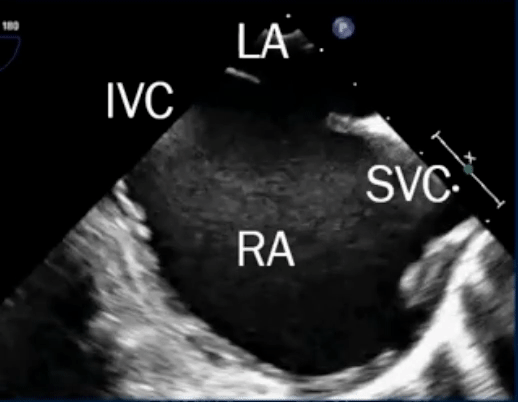

Sinus venosus defect

- Defects where the SVC/IVC reach the RA

- defect is a communication between one or more of the right pulmonary veins and the cardiac end of the superior vena cava (superior vena cava type) or the posterior-inferior atrial wall just above the inferior vena cava-right atrial junction (inferior sinus venosus defect) 1

- Most are SVC-type, i.e. superior sinus venosus defect in region of SVC-RA junction

- Can be difficult to see on TTE, ∴ TEE, CMR, or CT needed.

- TEE below shows bicaval view. To identify the superior sinus venosus defect (i.e. SVC type), you’ll want to pay attention to the SVC area as highlighted in this image.